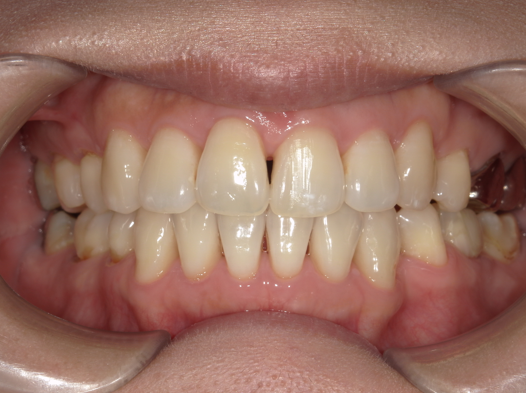

症例1:前歯のガタつきが気になる

| 患者様データ | 20代 女性 |

| 来院主訴 | 口元を下げたい。前歯のガタつきが気になる。 |

| 治療内容 | 口元を下げるために上下4本抜歯し、インビザラインにてマウスピース矯正を開始しました。かみ合わせを整えるためにゴムかけを行いました。 |

| 概算治療費 | 約90万円 |

| 治療期間 | 1年10ヶ月 |

| 通院回数 | 10回 |